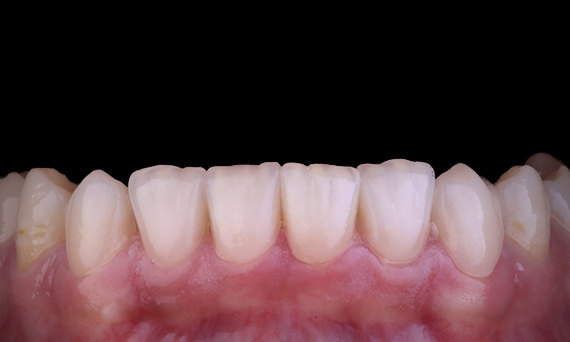

Het is vrij gebruikelijk om scheuren en breuken waar te nemen die verband houden met amalgaamrestauraties, vooral omdat ze groter worden omdat het “ongebonden” restauraties zijn. Veel van deze tanden zijn structureel aangetast en een zelfklevende, biomimetische aanpak is de ideale methode om deze tanden te herstellen. In het kader van een uitgebreider behandelplan is gepland dat dit kwadrant twee indirecte keramische onlays krijgt. De eerste en tweede molaren werden bij één bezoek gerestaureerd met CEREC Tessera, een geavanceerd lithiumdisilicaat.

Dr. Yo-Han Choi, Sydney, Australië